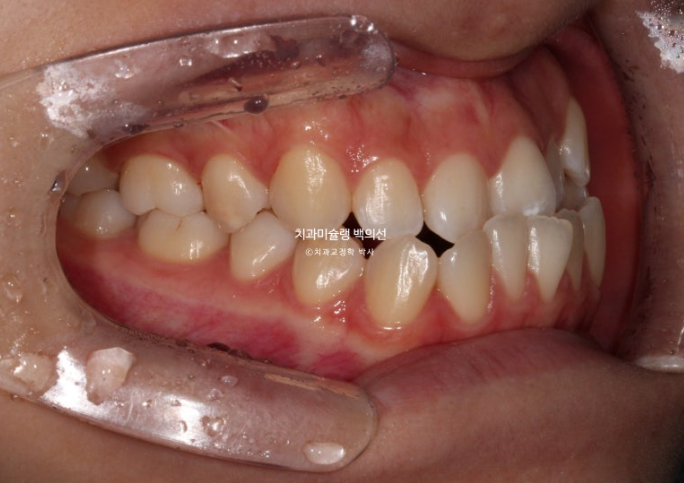

23.11~25.10

앞니가 거꾸로 물리는 반대교합이 해결되었습니다.